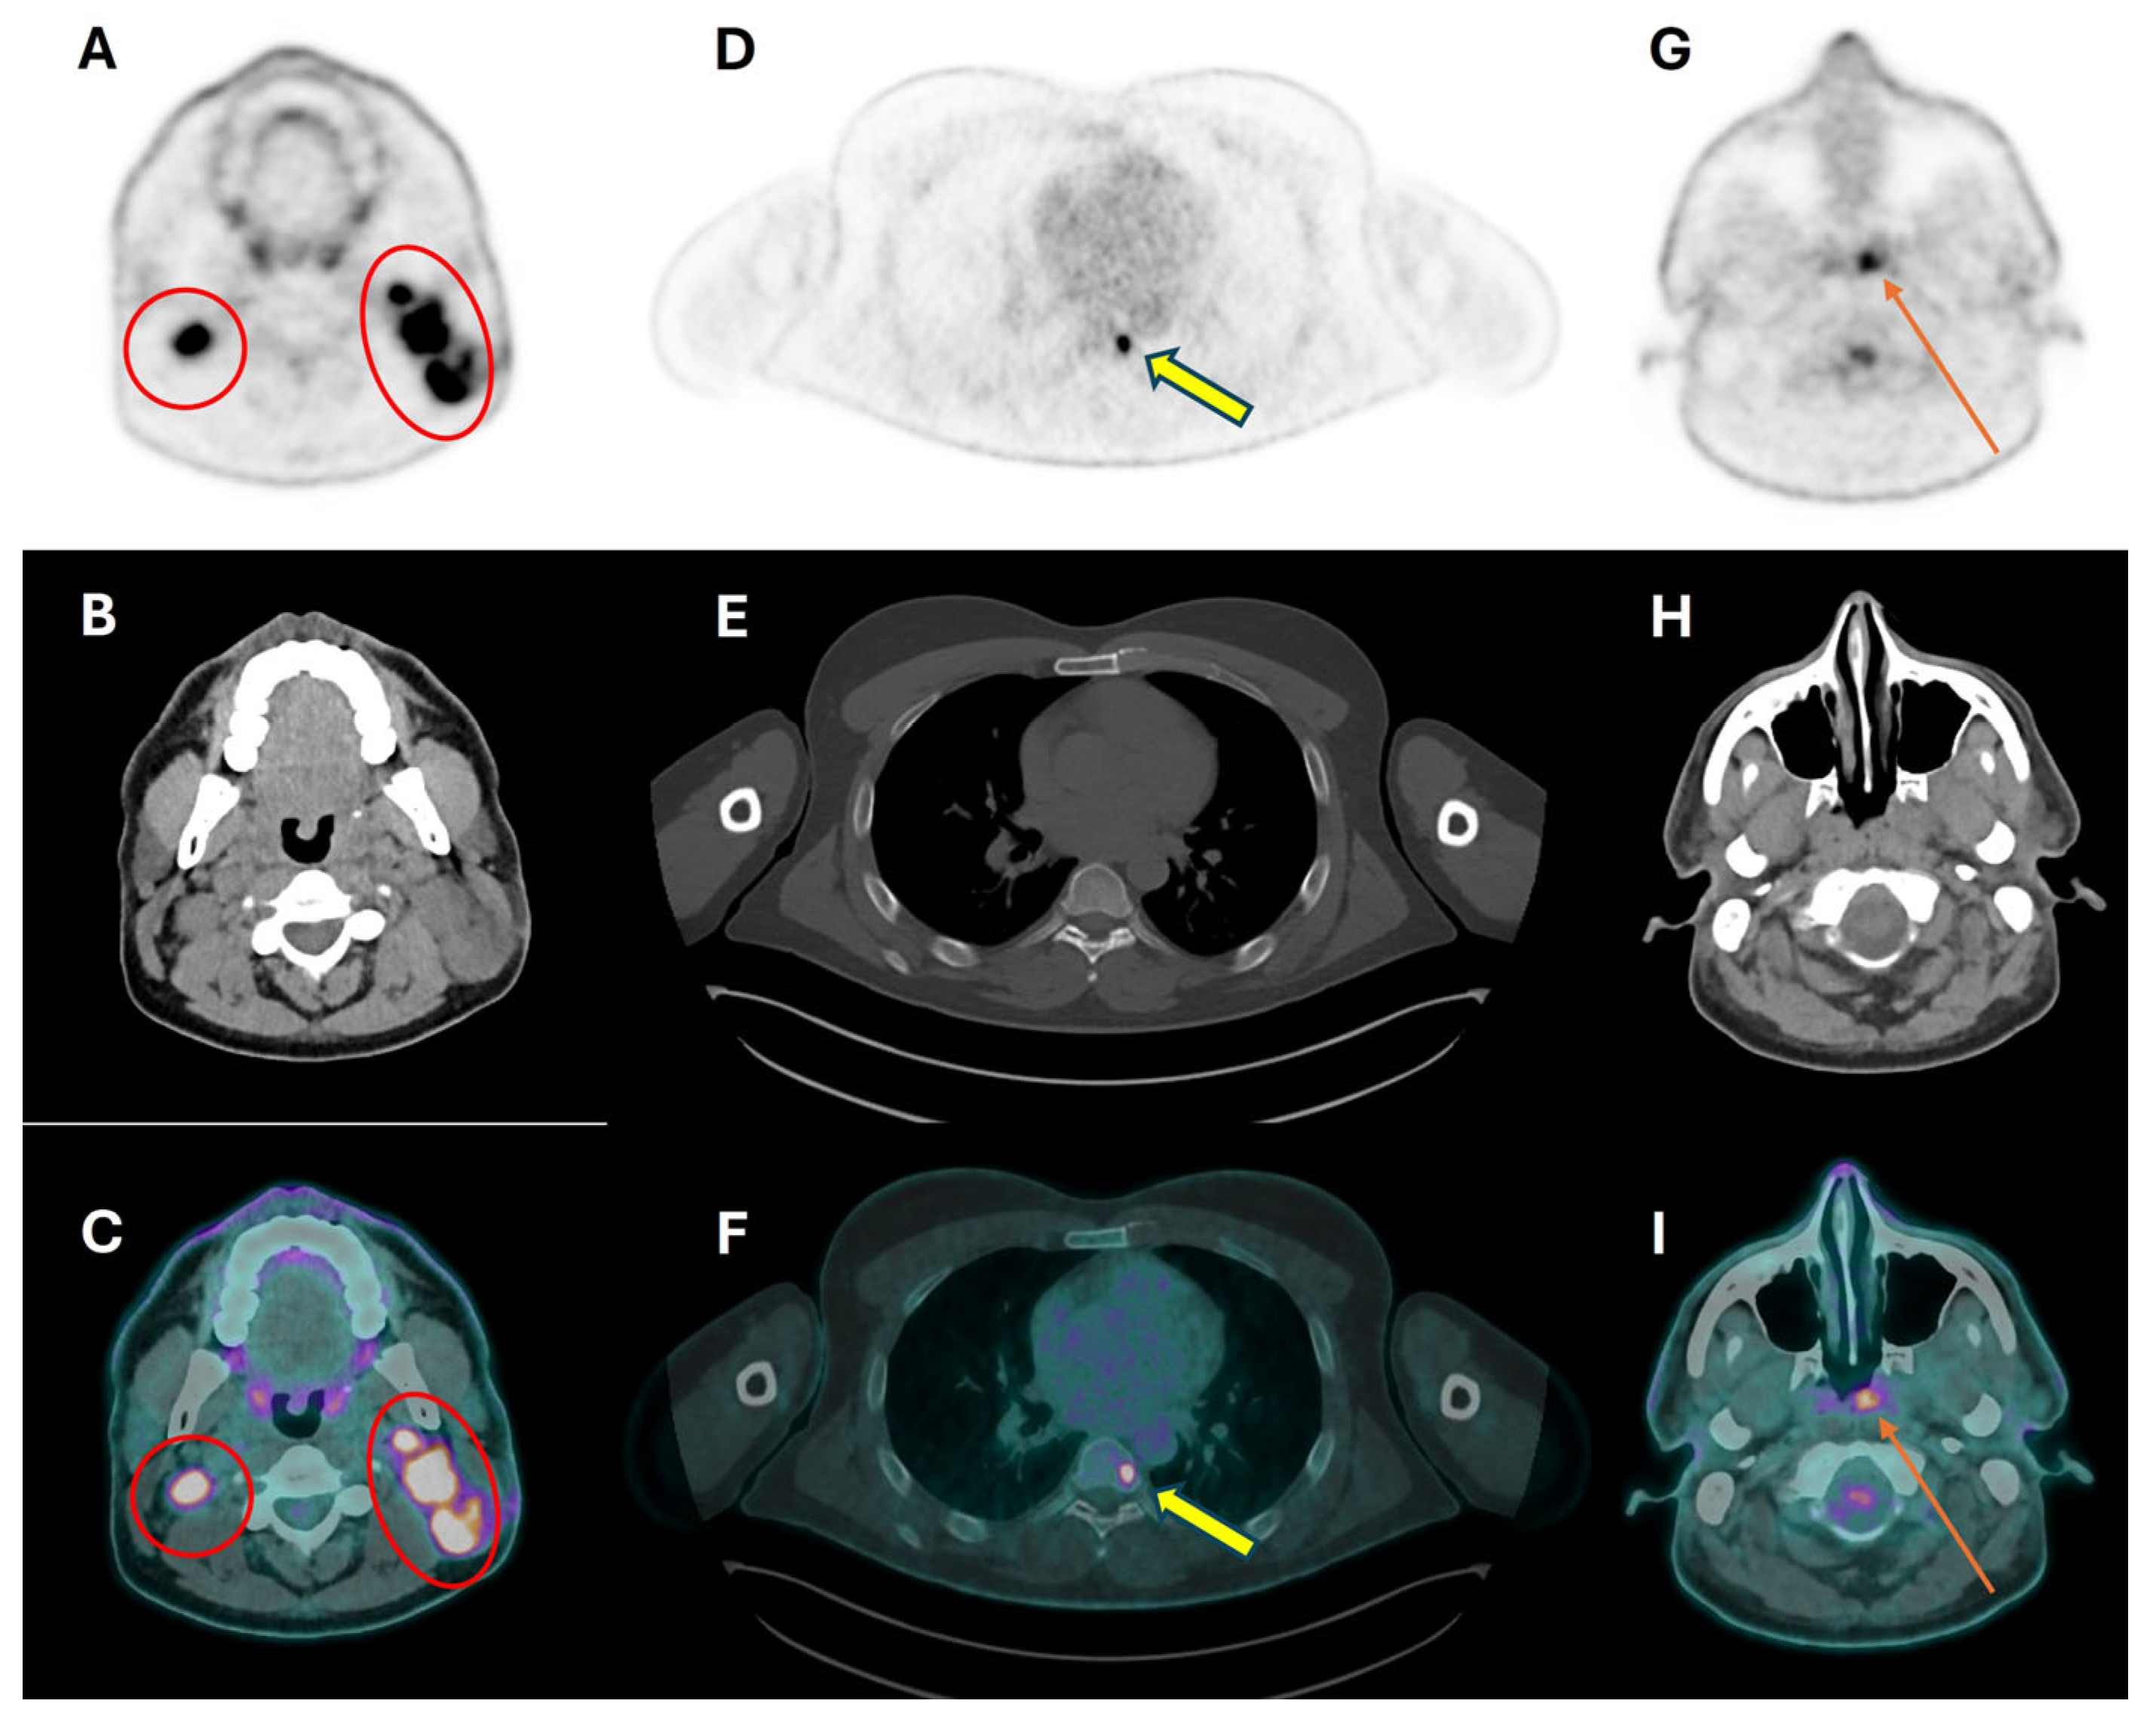

3.3. Distant Metastasis Assessment

3.4. Second Primary Tumor Assessment